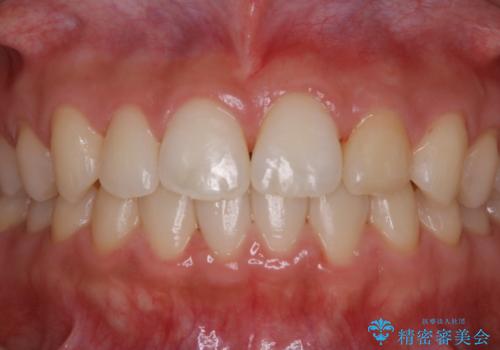

矯正治療終了後にPMTC(Professional Mechanical Tooth Cleaning)

- 矯正治療が終了したため、クリーニングでもきれいにしたいとのことでした。PMTC60分コースを行いました。

矯正治療やセラミックなどによる被せ物の治療終了のタイミングではクリーニングを行い、汚れや着色の除去、歯と歯の間・歯と歯肉との境目などのケアをしっかりすることをおすすめしています。

ご自身での歯ブラシ・セルフケアを行うと同時に、定期的なクリーニング(PMTC)を行うことで、いつまでも健康な歯を保つことができます。